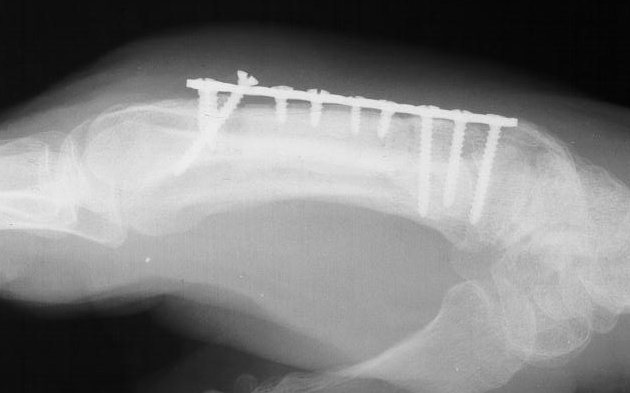

I removed this hardware, and used two mini condylar blade plates at right angles to resecure the distal bone juncture. This allowed more distal purchase while avoiding hardware placement beneath the metacarpal head extensor hood. I replated the proximal bone juncture although it looked clinically healed - not worth taking a chance.

Click for larger image

Final result, eight months postop, healed:

Healed.